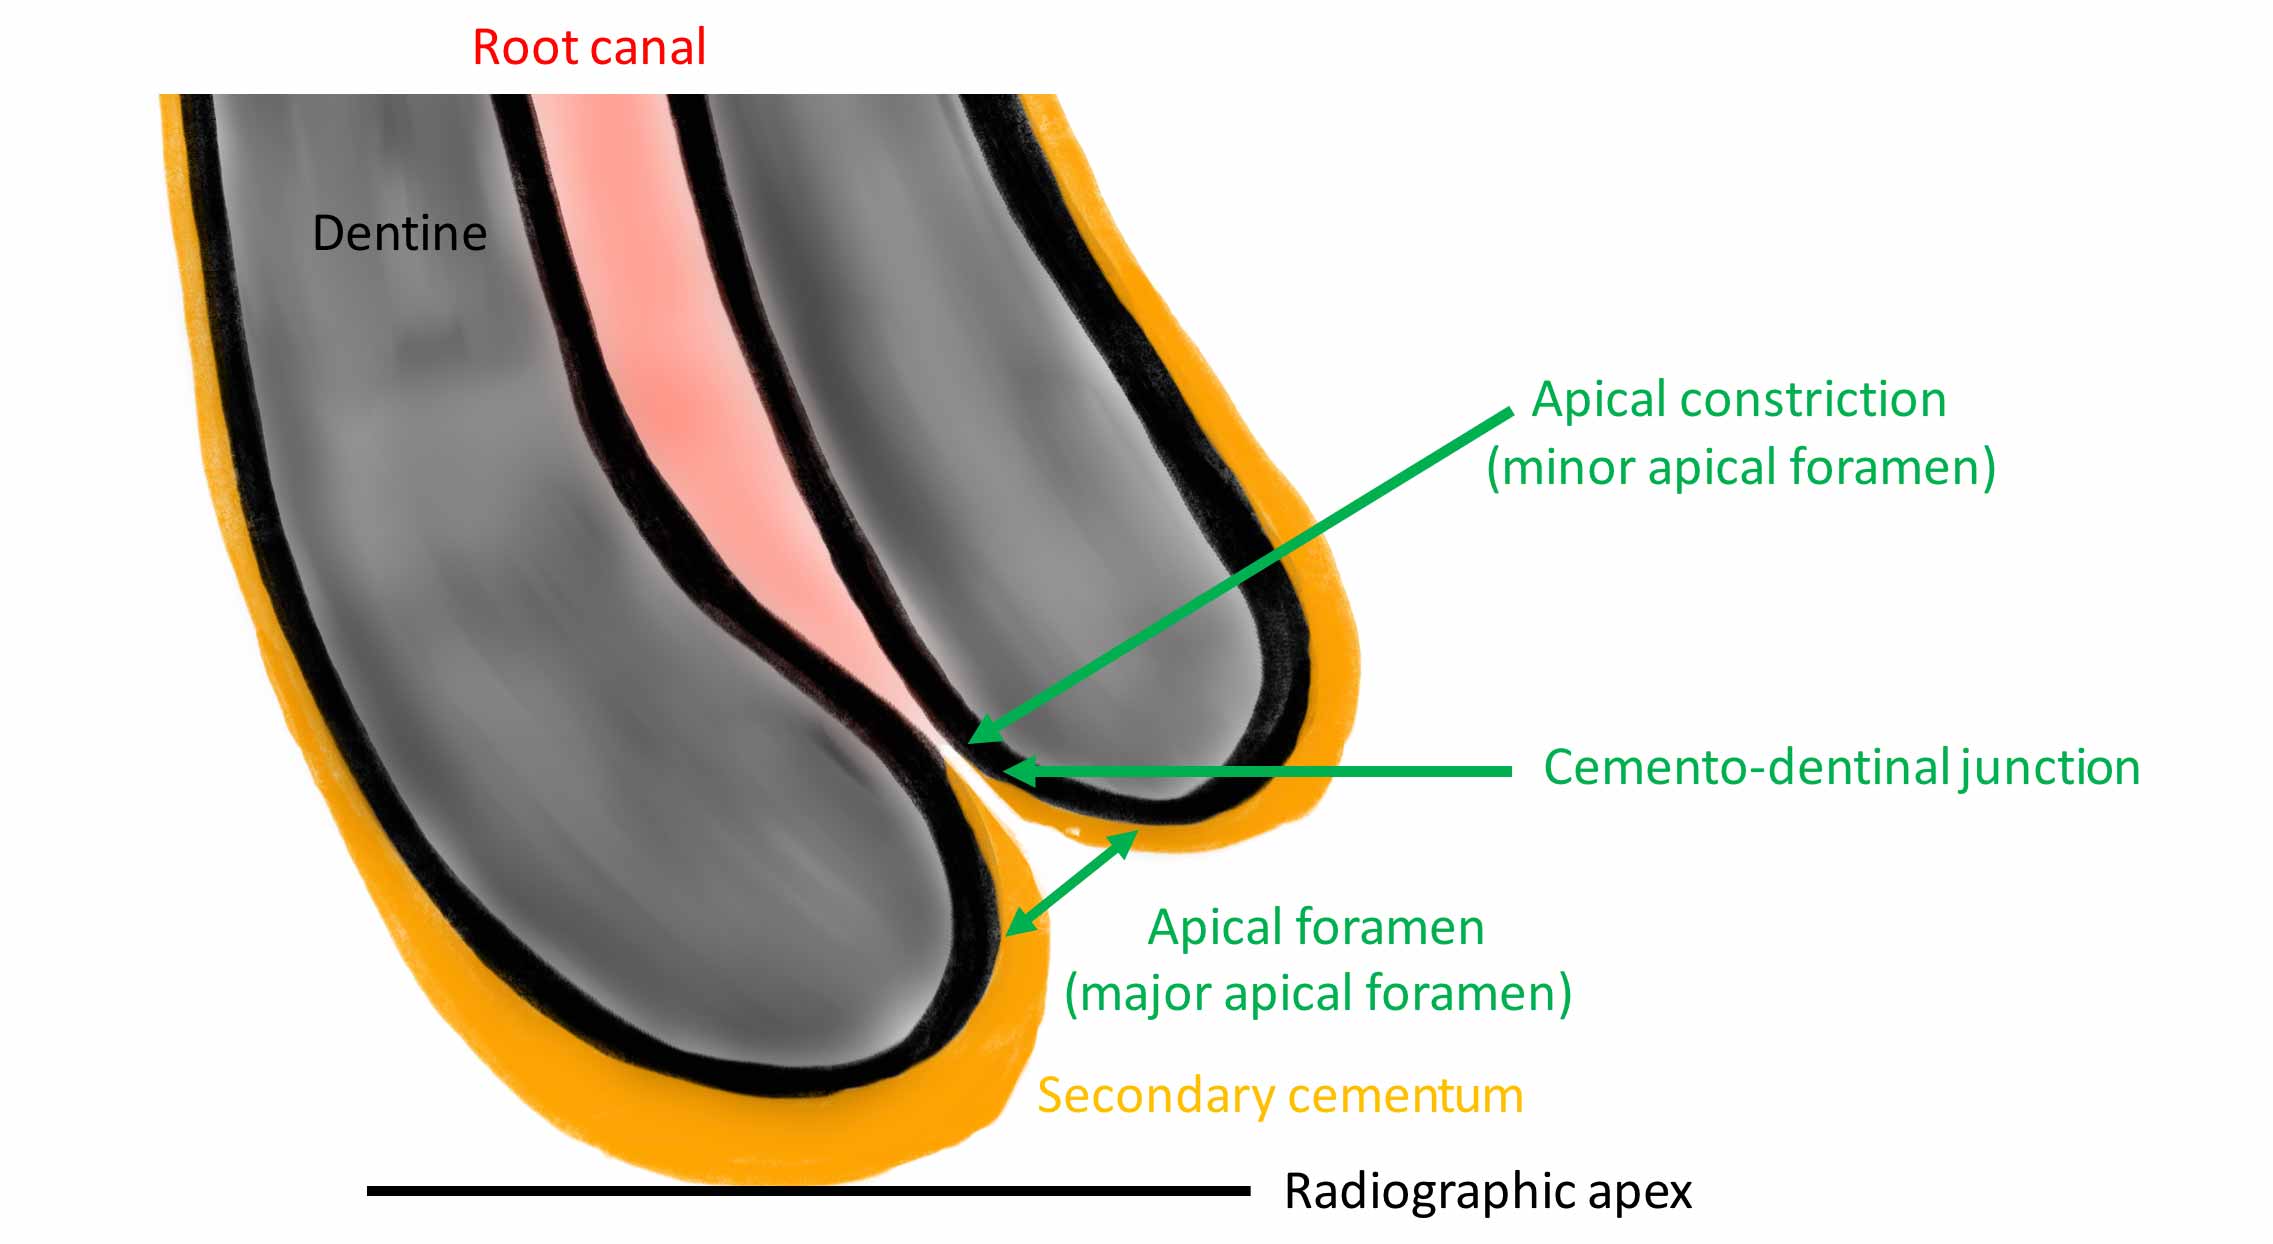

The narrowest part of the canal is the apical constriction or minor foramen. From this point the canal gradually widens to terminate at the apical foramen or major foramen (Figure 1).

The cemento-dentinal junction (CDJ) is the histological landmark where the pulp ends and the periodontal ligament starts. It is expected to lie at the apical constriction (AC) but it’s position can be irregular.

The working length (WL) is the length from a coronal reference point to the apical limit of the preparation. The optimal end point for root canal preparation and obturation is to the apical constriction. This in theory would create the smallest wound.

- The apical foramen is not always located at root terminus (Figures 1 and 2). There can be up to 3mm variation in 50-98% of roots. It is generally greater in posterior teeth

Figure 2a: Master cone radiograph. The apical foramen exits the root laterally on the mesial root. An apex locator is essential in these cases to determine the WL. b) Mid-fill radiograph - The distance between with apical constriction and root terminus increases with age due to secondary cementum deposition at the root apex (Figure 1)

One side of the apex locator is connected to the oral mucosa (via a lip clip) and the other side to the file. The circuit is completed (zero reading reached) when the file contacts the periodontal tissue at the CDJ (Figure 1).